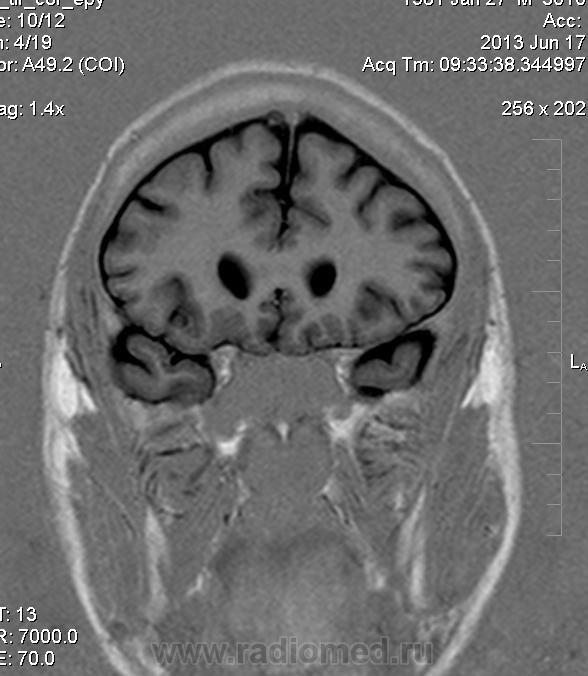

Мужчина 32 лет. Из анамнеза: перинатальное повреждение ЦНС, ДЦП, дизартрия, правосторонний верхний монопарез. С 16 лет приступы эпилепсии.

Аплазия прозрачной перегородки. Шизэнцефалия с открытыми краями в лобно-теменной области слева. Шизэнцефалия с закрытыми краями в лобной области справа? Утолщение коры по контуру расщелин и в области глазничной извилины правой лобной доли. Микрогирия? Гиперостоз костей свода черепа. Уважаемые коллеги, возможно я ошибаюсь, или есть еще аномалия?

сочетания отсутствия прозрачной перегородки и дисплазии ( разно степени выраженности) зрительных неровов  указывает на септоптическую дисплазию-нарушение развития в области средней линии , сопровождается мнггими другими структурными аномалиями, чаще шизэнцефалией.

На мой взгляд, полимикрогирия двусторонняя (конвекситальные отделы дорзальных отделов лобных долей и частично теменных, а также в базальном отделе полюса правой лобной доли) + закрытая шизенцефалия левой лобно-теменной области. Аплазия прозрачной перегородки (как признаки лобарной голопрозенцефалии).